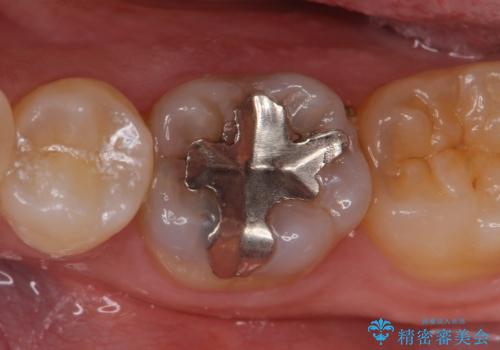

セラミックインレー しみる奥歯の治療